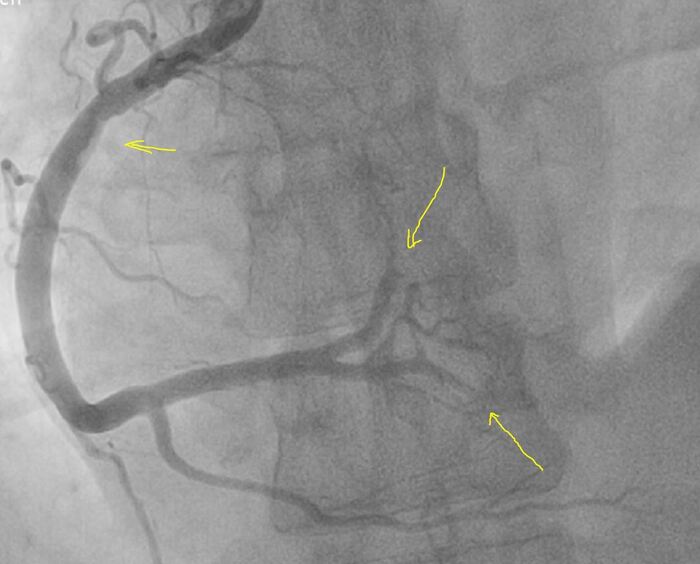

На коронароангиографии - левая коронарная артерия без поражения, правая - начальные признаки коронарного атеросклероза без значимого стенозирования, нестабильная атеросклеротическая бляшка с пристеночным тромбозом, осложненная дистальной эмболией в заднюю межжелудочковую и задне-боковую ветви.

ВИДЕО:

Более крупно место где все началось:

Красным зона пристеночного тромбоза, он неоднороден по плотности, рыхлый и отсюда мигрировали тромбы вниз, закупорив дистальные ветви -> как итог инфаркт.

Лечение в рентгеноперационной: пятикратно тромбаспирация (удаление тромба) специальным катетером - удалось полностью удалить тромбы из ЗБВ и частично из ЗМЖВ (Тип аспирата: крупные красные тромбы). Ввиду характера поражения в самой правой артерии (пристеночный тромбоз без значимого стенозирования) решено обойтись без стентирования - начато введение препарата Агграстат (тирофибан) по схеме с продленной инфузией, который избирательно блокирует тромбообразование (блокатор 2Б-3А рецепторов).

Финальный результат: